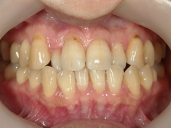

矯正歯科 治療前 正面

矯正歯科 治療後 正面